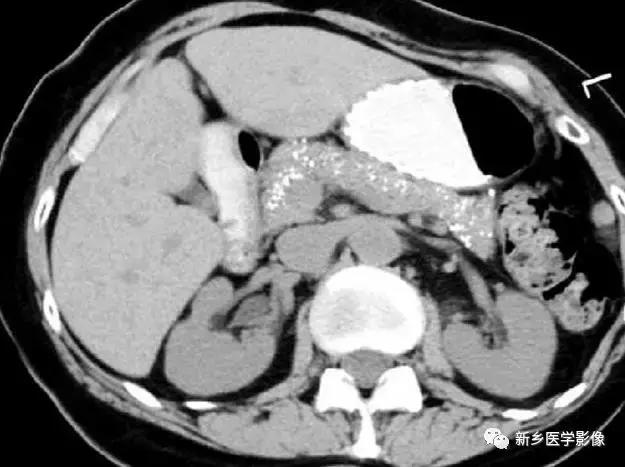

6、动脉钙化动脉瘤